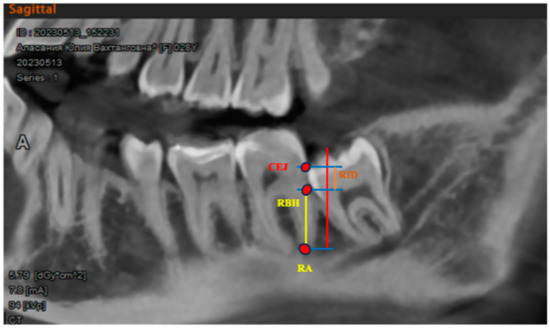

Radiology parameters such as “radiographic infrabony defect” (RID) and “radiographic bone height” (RBH) were analyzed on CVCT [33] (Figure 5). Parameters were examined immediately after the extraction at 12 weeks and 24 weeks to assess the bone regeneration process.

The radiographic bone height (RBH) was determined as the distance between the uppermost point, where the M2 distal root and the mesial wall of extraction socket intersected, and the root apex (RA). The radiographic infrabony defect (RID) was determined as the distance from the RBH to the cementoenamel junction to evaluate bone regeneration within the socket.

Figure 5. Radiology parameters: radiographic infrabony defect (RID); radiographic bone height (RBH); root apex (RA); cementoenamel junction (CEJ).